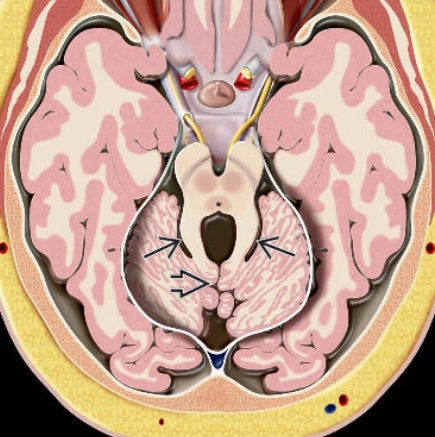

• Bất thường não sau

• DỊ TẬT DANDY-WALKER (DANDY-WALKER CONTINUUM)

• TẬT DÍNH TRÁM NÃO (RHOMBENCEPHALOSYNAPSIS)

• LOẠN SẢN TIỂU NÃO KHÔNG PHÂN LOẠI (UNCLASSIFIED CEREBELLAR DYSPLASIA)

• CÁC RỐI LOẠN LIÊN QUAN ĐẾN HỘI CHỨNG JOUBERT (JOUBERT SYNDROME RELATED DISORDERS - JSRD)

• THIỂU SẢN TIỂU NÃO (CEREBELLAR HYPOPLASIA)